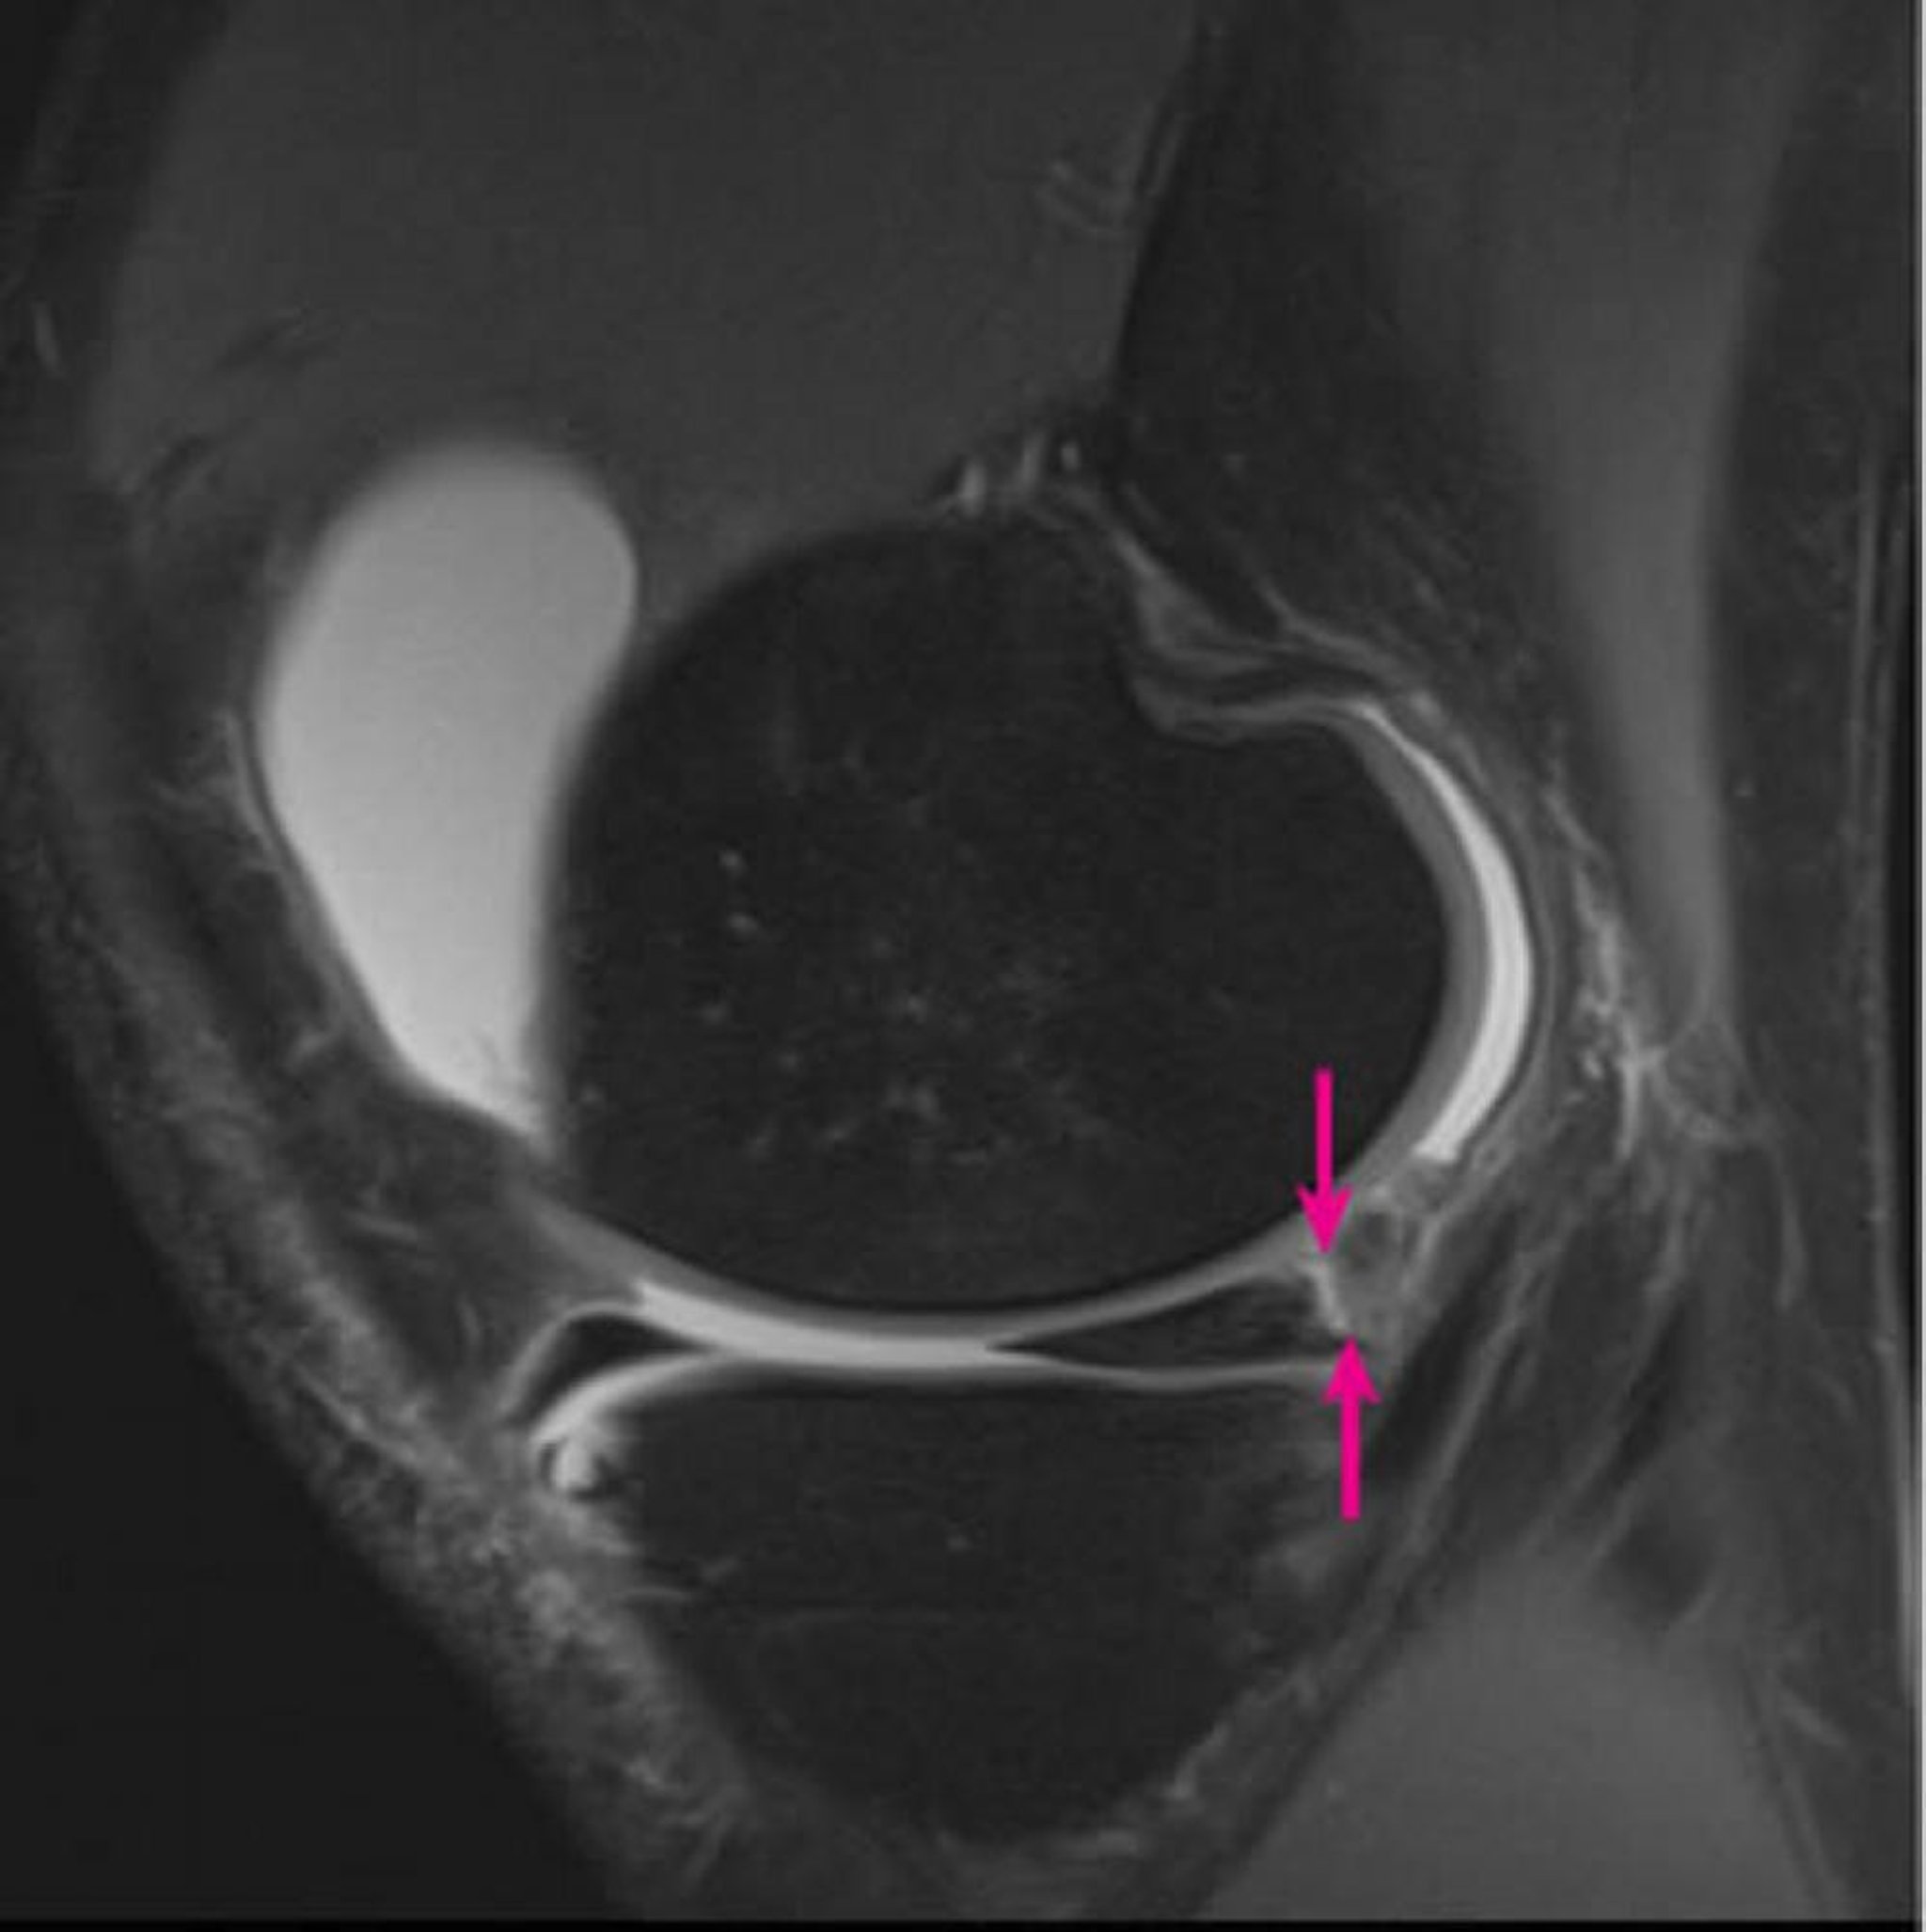

Sagittal proton density–weighted 3-tesla magnetic resonance image of the right knee shows meniscocapsular separation involving the medial meniscus posterior horn (arrows) and a large knee joint effusion (white).

Image courtesy of Hakan Ilaslan, MD.